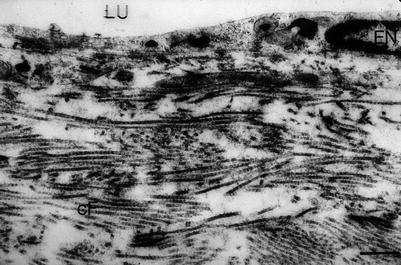

In normal abdominal thoracic ducts, the endothelium was smooth. The endothelial cells were closely connected, sometimes showing microvilli. Collagen fibers type I showed an exact arrangement in alternate directions. In between collagen fibers of type III were seen. Within the deeper layers of the lymphatic wall, fibrocytes, some capillaries, and single fat cells were seen.

Between days 40 and 60, within the wall caverns appeared, together with a massive infiltration of activated lymphocytes, plasma cells, macrophages, and erythrocytes. The wall however remained stable because of the new endothelium and the subendothelial tissue containing a continuous basal membrane, structured collagen fibers type I, and differentiated muscle cells (Figs. 2.14, 2.15, and 2.16).

Fig. 2.14

Allogeneic abdominal thoracic duct graft of rat. 40 days after grafting (ultrathin section, 1000-fold magnification) (E endothelial cell, LU lumen, cF collagen fibers)

Fig. 2.15

Allogeneic abdominal thoracic duct graft of rat. 40 days after grafting (scanning electron microscopy, 440-fold magnification). LU lumen, EN endothelium, cF collagen fibers, Faden suture)